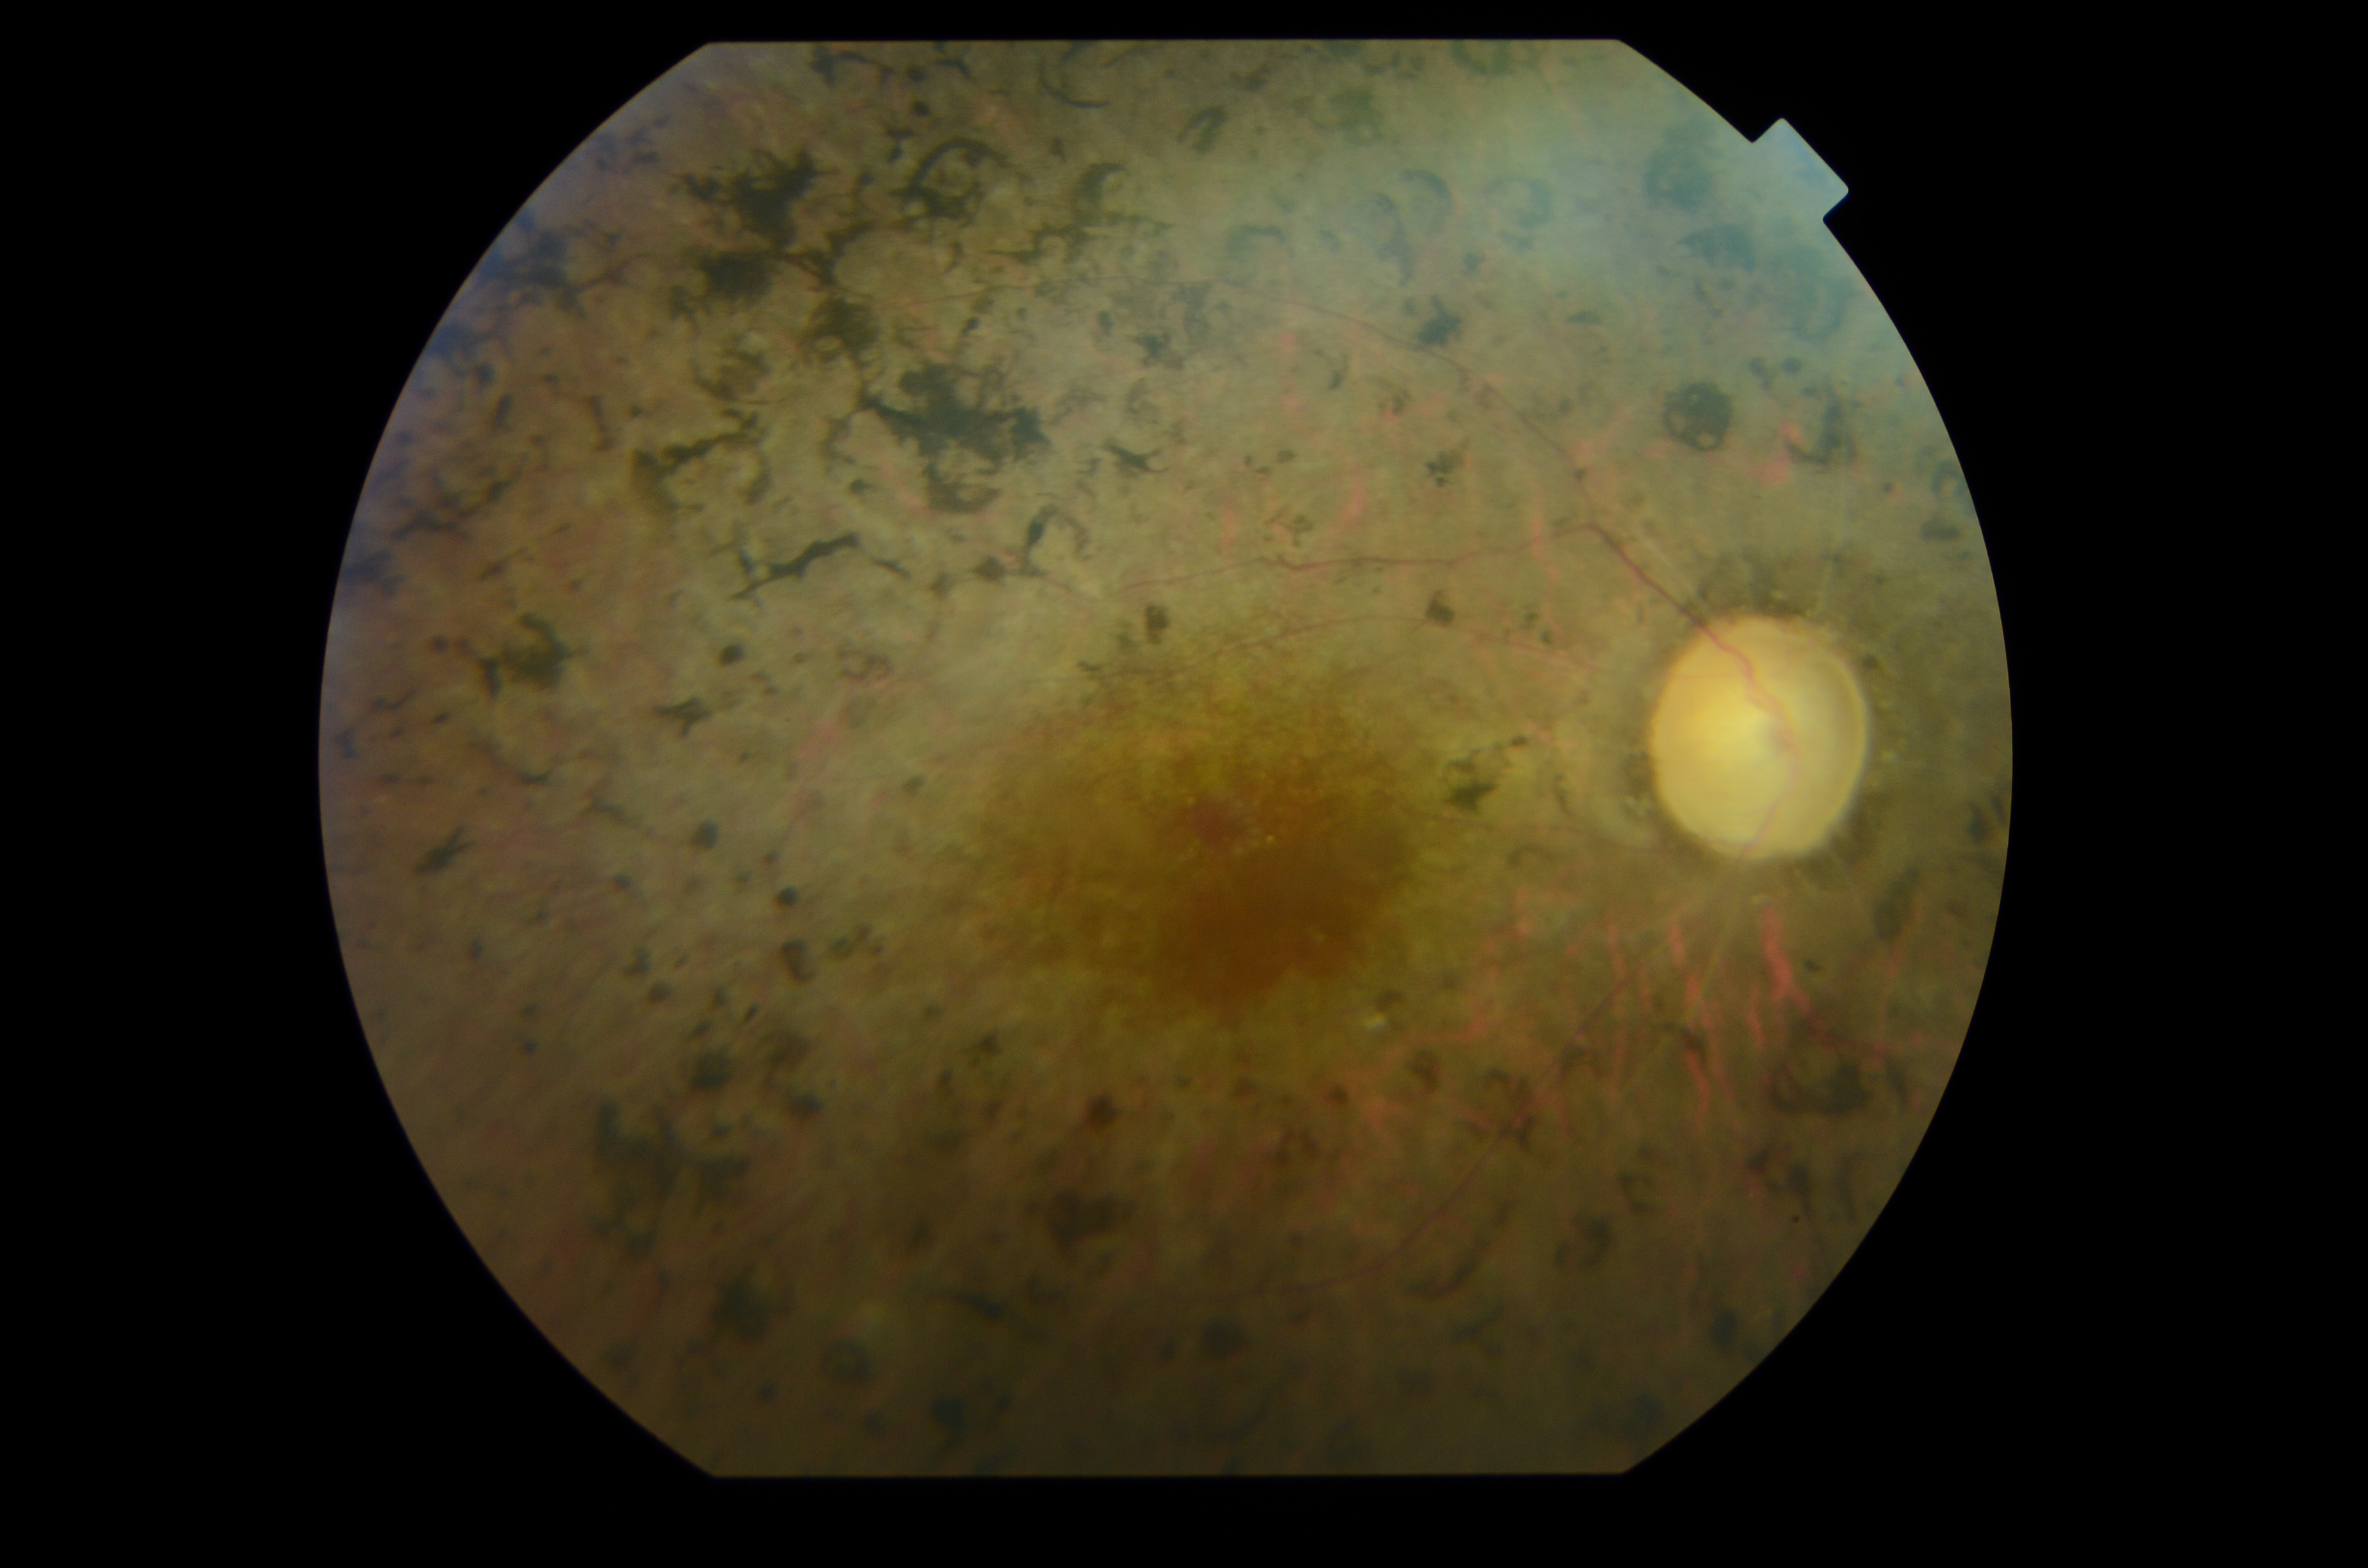

Erretinosi pigmentarioa erretinaren gaixotasun hereditario eta endekapenezkoa da, prebalentzia baxukoa, eta gaixotasun arraroen barnean sartzen da. Nerabezaroan, pazienteek ikusmen-galera sentitzen dute gauez; ikus-eremu periferikoaren ikusmen-galera handituz doa, eta, azkenik, ikusmen zentrala ere gutxitzen zaie. Gaixotasuna mutazioek eragiten dute. “Gaur egun, 3.000 mutaziotik gora ezagutzen dira, erretinosi pigmentarioarekin lotutako 107 genetan. Kasuen % 65 baino ez da ezagutzen, eta gainerako % 35a aurkitzeko dago oraindik”, dio Cristina Irigoyen oftalmologo eta UPV/EHUko irakasleak.

Orain arte gaixotasunak ez zuen tratamendurik, baina, gaur egun, badira zenbait tratamendu garapen-fasean, gaixotasunaren etapa desberdinetarako. Azken urteotan, aurrerapen handiak ari dira egiten terapia genikoan: tratamendu farmakologikoak bilatzen ari dira mutazio jakin batzuetarako. Terapia genikoan lortutako aurrerapenek “sekulako garrantzia eman diote pazienteek beren diagnostiko genetikoa izateari; hala, paziente batek duen mutazio jakin batentzat tratamendua aurkitzen den unean bertan, pazientea tratamendua jasotzeko irteera-lerroan egongo da edo saiakuntza klinikoetan parte hartu ahal izango du”, azaldu du Irigoyen doktoreak. Zehazki, “20 saiakuntza kliniko baino gehiago daude martxan, eta paziente gipuzkoarrekin egindako ikerketari esker hauteman dugu Donostia Ospitaleko 32 paziente balia litezkeela saiakuntza kliniko horien emaitzez”, adierazi du.